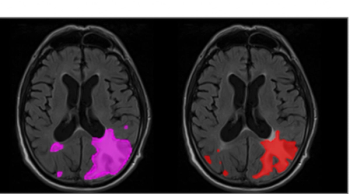

The adjunctive use of AI software led to 16 percent and 10 percent increases in sensitivity rates for the detection of ARIA-E and ARIA-H, respectively, in patients with Alzheimer’s disease, according to newly published research.